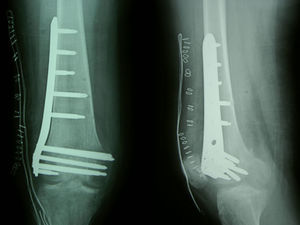

TratamientoLa fractura fue estabilizada quirúrgicamente 48h después mediante técnica mínimamente invasiva (MIPO) (fig. 4); se tomaron dos muestras de biopsia con trócar para estudio anatomopatológico, que confirmó posteriormente el diagnóstico de síndrome de edema de médula ósea sin áreas de necrosis trabecular (fig. 5).

En el último control clínico-radiológico (14 semanas tras la intervención), la enferma se encontraba asintomática, realizando carga total, con un balance articular 5°-110°. El control radiológico mostró consolidación de la fractura y restablecimiento de la densidad ósea.